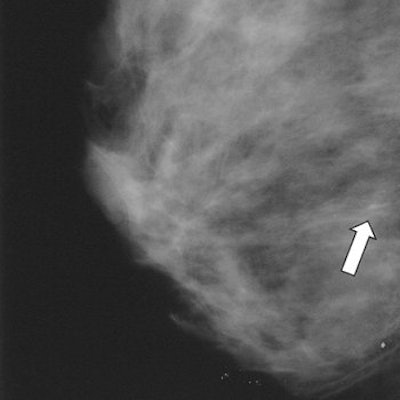

| Ductal carcinoma in situ in left breast of 44-year-old woman. Oblique view mammogram and mammographic magnification view of surgical specimen shows cluster of punctate calcifications (arrow) close to hookwire. |

Of the 112 lesions, 33 were ductal carcinoma in situ (DCIS) and 42 were either invasive ductal carcinoma (IDC) or invasive lobular carcinoma (ILC). All presented as microcalcification clusters with and without opacity.

The diagnosis of DCIS was confirmed by pathology, and 87.8% of those 33 lesions showed enhancement after contrast agent injection, the authors stated in their results. There were seven false-negative cases, all of which had presented mammographically as microcalcifications. The sensitivity of MRI for DCIS was 79%.